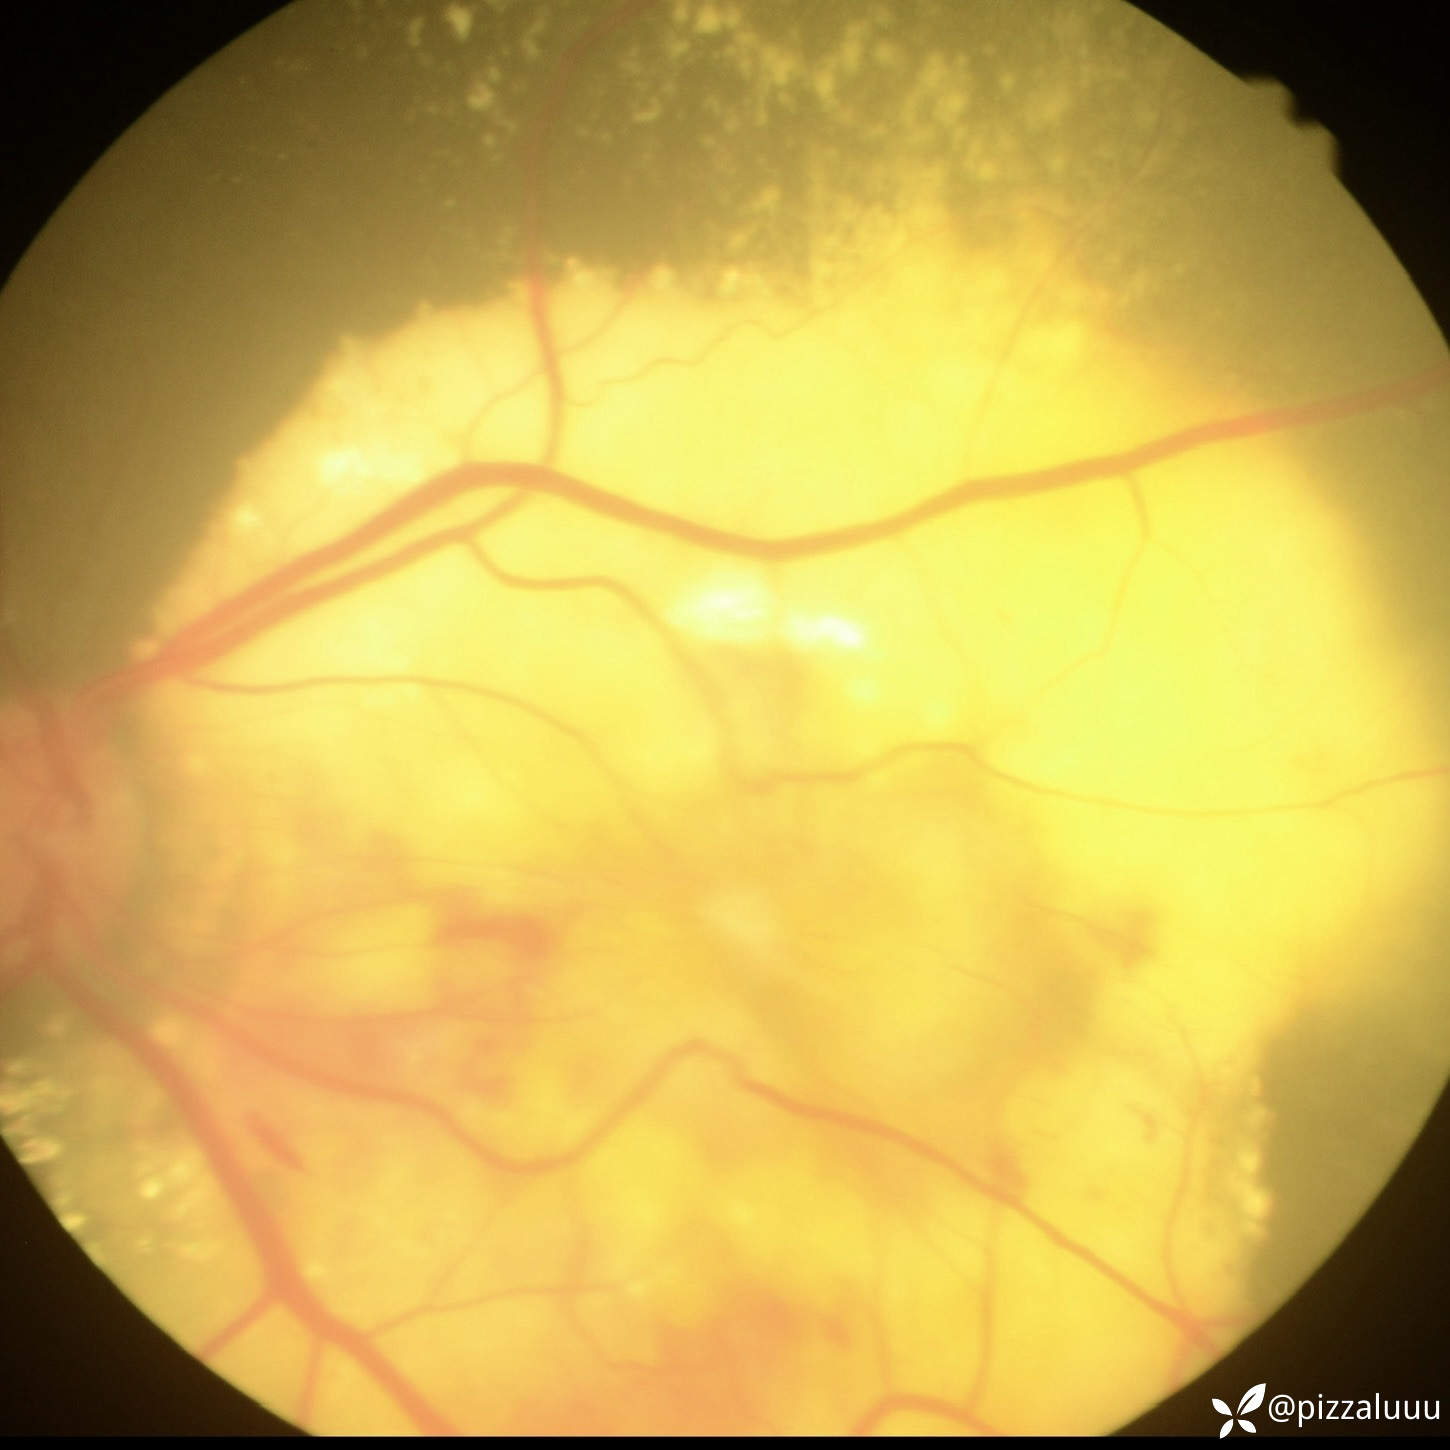

今天补充了FFA、AF和眼底照相。很典型的coats,后极部视网膜可见块状不规则而隆起的黄色渗出。AF可见病灶处低自发荧光。FFA所见:视网膜毛细血管扩张迂曲及异常血管形态,以小动脉明显,管壁呈囊样扩张,有梭形、串珠样动脉瘤。大片无灌注区。异常血管早期渗漏明显,形成强荧光斑,晚期荧光融合。由于大片黄白色渗出位于外丛状层,对视网膜血管荧光影响不大。可看到脉络膜背景荧光遮蔽。